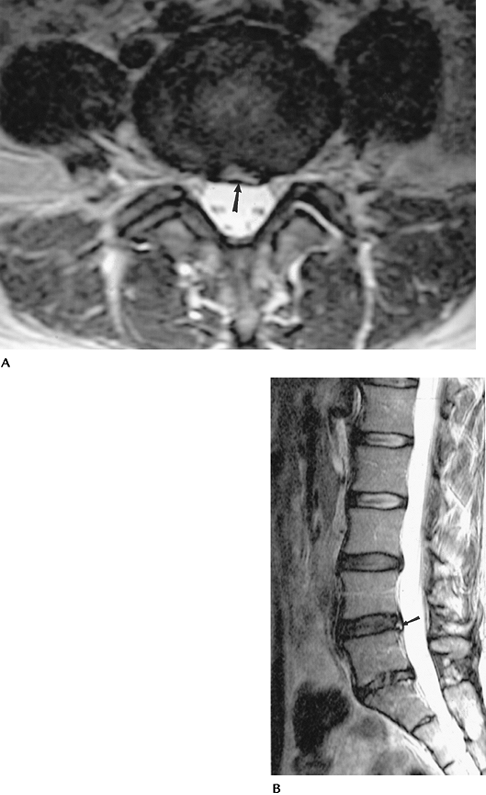

FIGURE 3-52 Lumbar disc protrusion at L4–5. Axial (A)

T2-weighted image demonstrates a focal left posterolateral disc protrusion flattening the left ventral lateral aspect of the thecal sac (arrow). On the sagittal image (B) there is a focus of increased T2 signal intensity in the posterior annulus (arrow) compatible with an annular tear. |